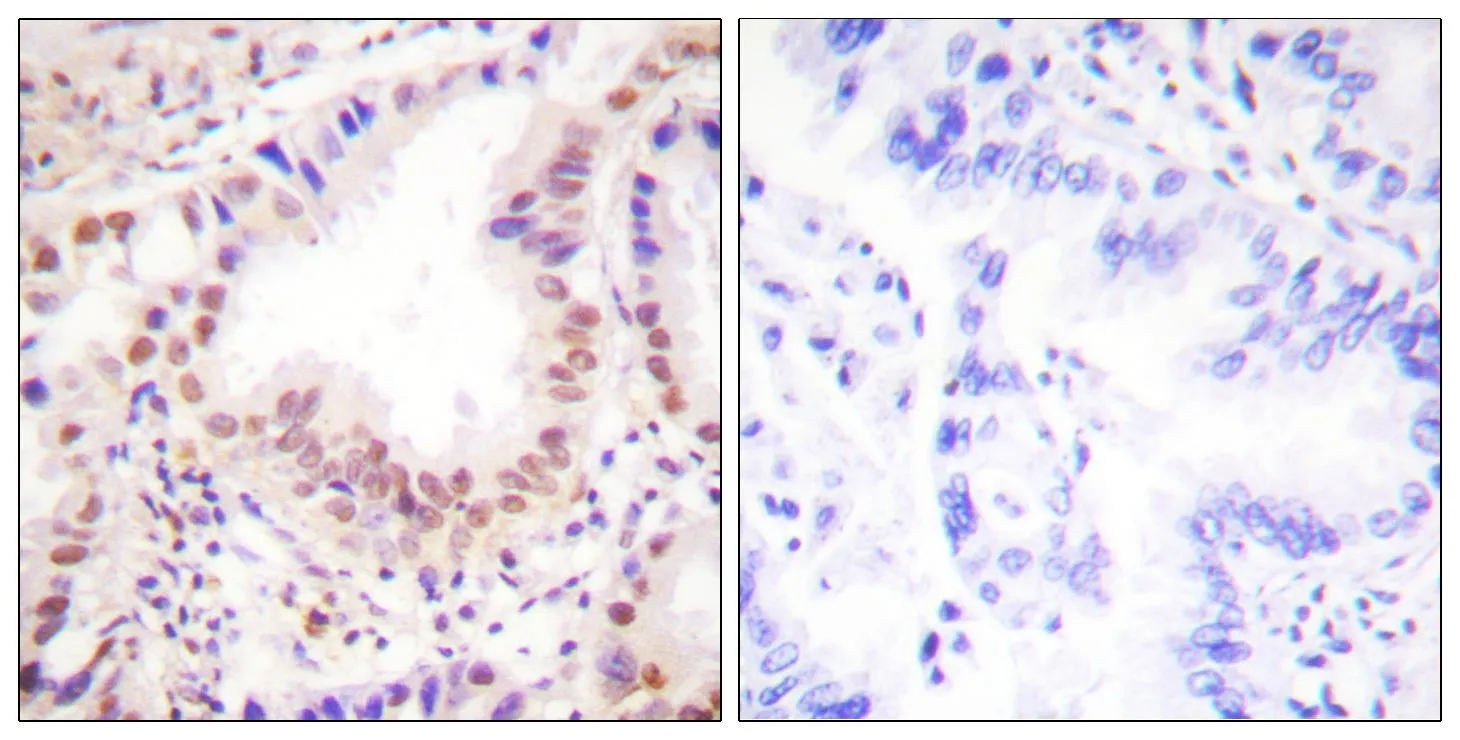

ETS1 Rabbit Polyclonal Antibody

Cat: APRab10649